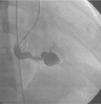

The most frequent symptoms were murmur and/or fatigue. All fistulas were congenital. Five patients (42%) had concomitant cardiac disease: pulmonary atresia with intact ventricular septum (1), patent ductus arteriosus (1), ostium secundum atrial septal defect (1), stenotic bicuspid aortic valve (1), and critical pulmonary stenosis operated in the neonatal period (1). Selective angiography was performed to delineate the anatomy of the fistula(s), which were embolized in the most distal part, sparing all the collateral branches. In one patient an arteriovenous loop was formed through the fistula, embolizing the terminal part of the fistula from the right atrium. The patients were heparinized (100UI/kg in children and 5000UI in adults) and were subsequently monitored by assessing activated coagulation time. Three patients had two fistulas, while the others had a single lesion. All fistulas were hemodynamically significant. They originated in the territory of the right coronary (10), left coronary (3) and circumflex (2), draining into the right ventricle (5), pulmonary artery (6), right atrium (2) coronary sinus (1) and left ventricle (1). Embolization materials included 15 standard coils in three patients, a Jackson® coil in one patient (Figures 1–3), 27 microcoils in 11 patients (18 standard microcoils in seven patients and nine GDC microcoils in four patients), and an Amplatzer® duct occluder in one patient (Figures 4–7). The GDC microcoils, both standard and complex, deserve particular mention, as release of these devices is controlled by electrolysis. The procedure is thus reversible up to the last stage of release, following confirmation of correct positioning. An Amplatzer® cardiac plug was tested in one patient but was not released due to its unsuitability for the lesion.